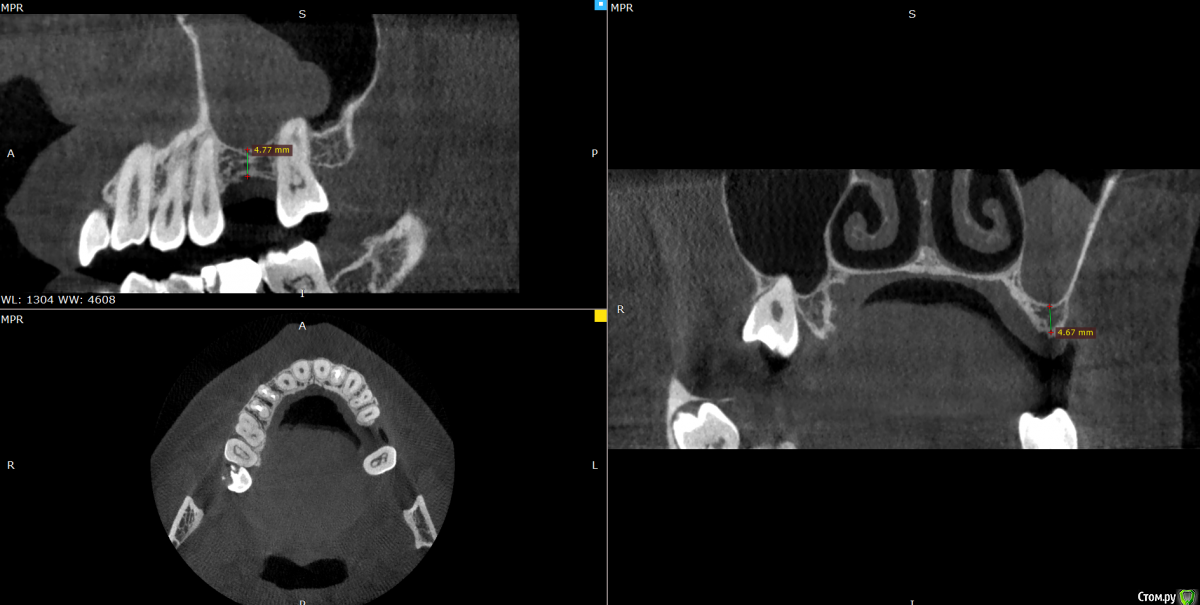

Valerkaa Опубликовано 14 декабря, 2019 Автор Поделиться Опубликовано 14 декабря, 2019 ну и кейс №2, чтобы не плодить темы. Пациентка планирует имплантацию в области 1.6, на КТ вот такая штука в пазухе. Нужен синус, отправила лечиться к Лорам. Это КТ на сегодня, т.е после лоров, около 4 месяцев назад была примерно такая же картина. Что делать, пусть ищет хорошего Лора? Жалоб со стороны пазухи нет. Ссылка на комментарий

Valerkaa Опубликовано 15 декабря, 2019 Автор Поделиться Опубликовано 15 декабря, 2019 Большое спасибо. Вот с размерами. №1 и №2 Ссылка на комментарий